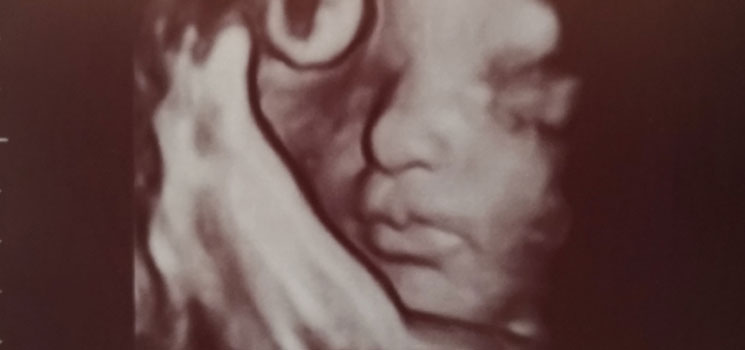

Muss ich mir wieder Sorgen machen? - Tagebücher aus der Schwangerschaft von Lina aus Traunstein